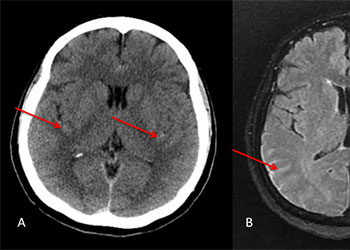

Brain:

Brain Metastasis

Author: Michael Brisman M.D., F.A.C.S., Read More!